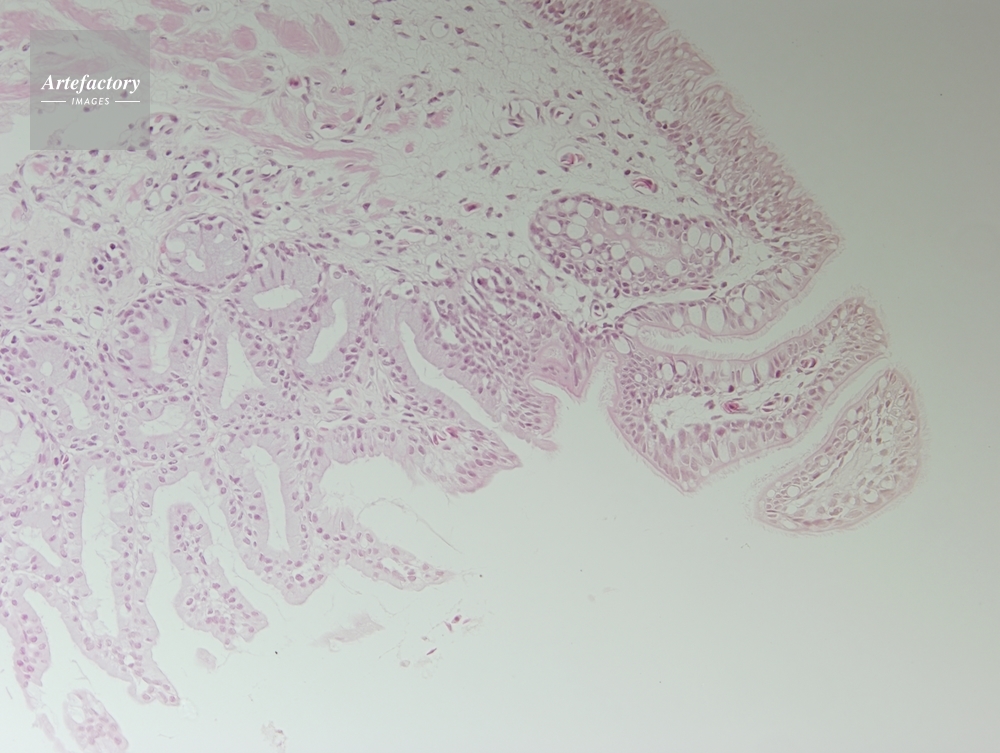

| 作品タイトル | カエル,舌 | モデルリリース | なし | |

| 作家 | OLYMPUS CORPORATION Technolab | プロパティリリース | なし | |